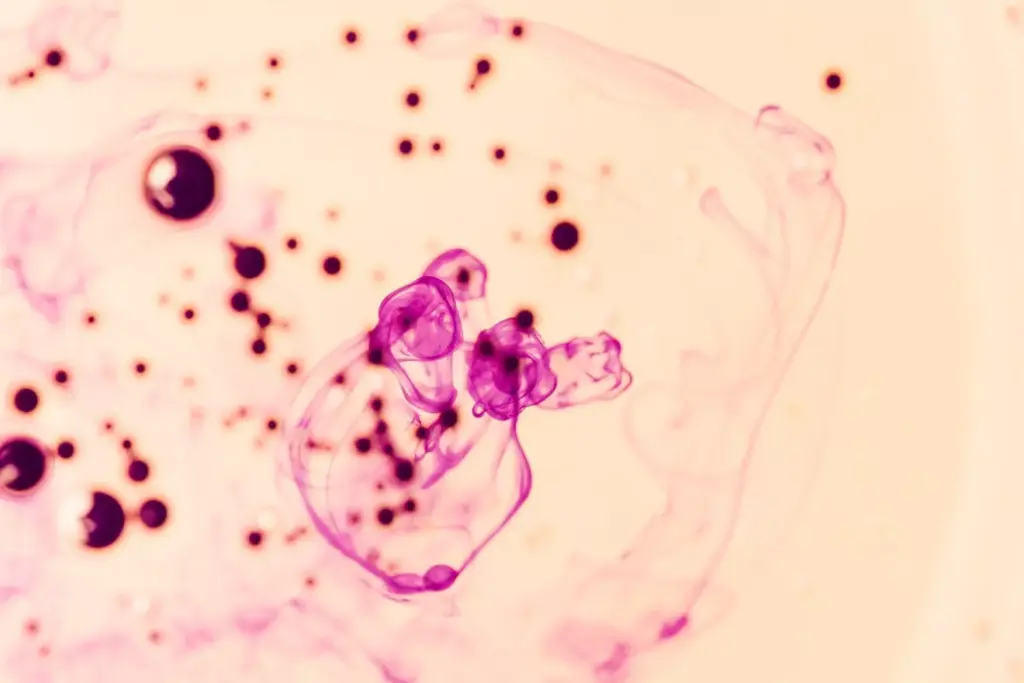

B cells are round and about 7-12 micrometers in size. They have a big nucleus and a small amount of cytoplasm. This shows they are very active in making proteins and dividing.

The cytoplasm of B cells has important organelles like the endoplasmic reticulum and Golgi apparatus. These help in making and sending out antibodies. This highlights their role in fighting infections.

B cells have special markers on their surface. These include CD19, CD20, and CD21. They help B cells grow, get activated, and change into different types.